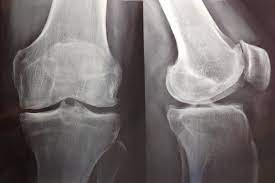

Efectividad a corto y largo plazo de las infiltraciones con corticoides en dolencia osteoarticular. Estudio prospectivo a 2 años

Las infiltraciones con corticoides son muy efectivas y seguras a corto plazo. Su efectividad disminuye progresivamente hasta los 2años, siendo el resultado muy variable según la dolencia. Atencion Primaria, marzo de 2025